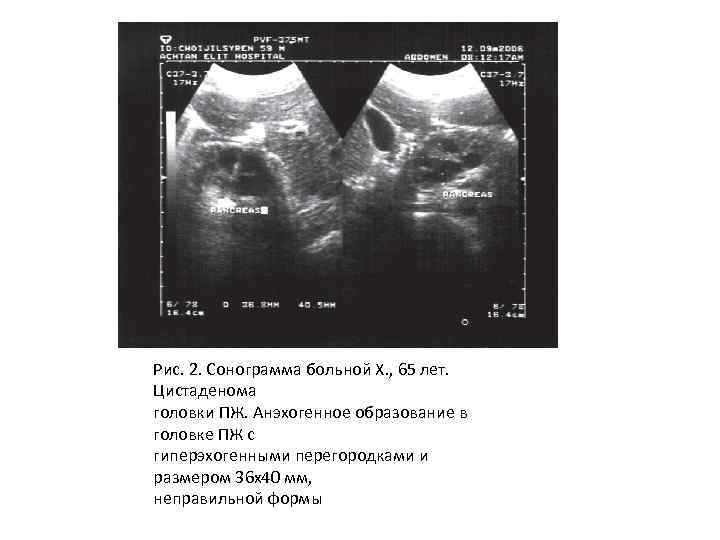

Рис. 2. Сонограмма больной Х. , 65 лет. Цистаденома головки ПЖ. Анэхогенное образование в головке ПЖ с гиперэхогенными перегородками и размером 36 х40 мм, неправильной формы